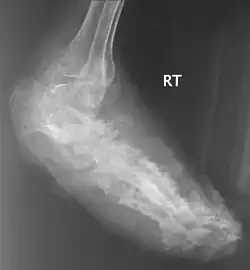

| An infected foot | |

X rays and ultrasonography may be carried out to assess the extent of the disease. X rays findings are extremely variable. The disease is most often observed at an advanced stage that exhibits extensive destruction of all bones of the foot. Rarely, a single lesion may be seen in the tibia where the picture is identical with chronic osteomyelitis. Cytology of fine needle aspirate or pus from the lesion, and tissue biopsy may be undertaken sometimes.[11] Some publications have claimed a "dot in a circle sign" as a characteristic MRI feature for this condition (this feature has also been described on ultrasound).[14]